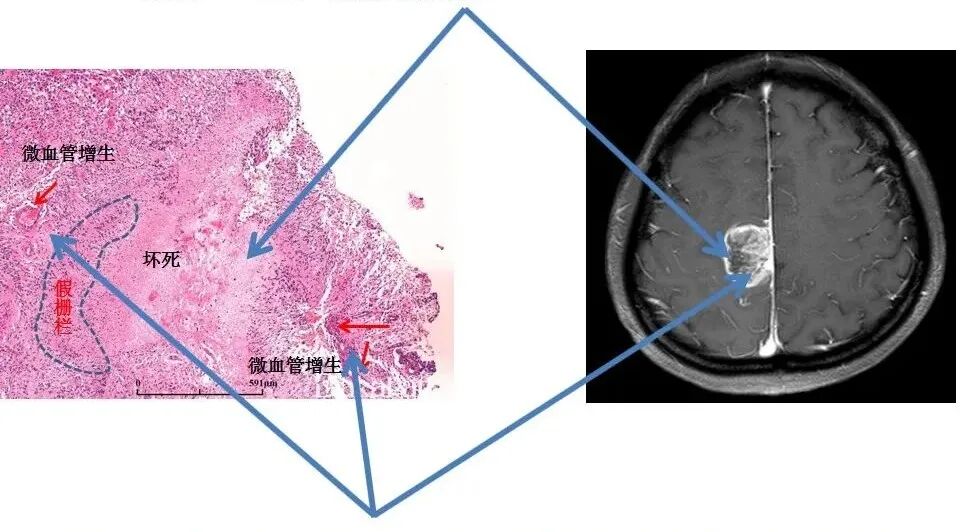

怎么买病理图文这些影像征象背后的病理基础,今天才知道!_https://www.jmylbn.com_新闻资讯_第3张

A、假栅栏的绘图,说明了环绕坏死区域的花环状核阵列

B、神经胶质母细胞瘤中的“伪足性坏死”是一种包含核固缩的不规则肿瘤坏死灶,周围的多细胞肿瘤核(箭头)的环状(假栅栏样)排列拥有属性。注意肿瘤血管(v)。

C、用图示的方式描绘了一个假栅栏形成的过程。胶质母细胞瘤的生长刺激新生血管生成。血管紧张素2的表达导致内皮损伤,进而引起血管闭塞和缺氧。细胞无法抵抗缺氧,形成凝固性坏死的病灶。然而,其他细胞以波动形式迁移到缺氧区的周围,形成假分化。迁移性缺氧细胞分泌血管内皮生长因子,蛋白酶和其他因素,进一步引起微血管增殖和增强对缺氧区域的侵袭力。后者的影响促使胶质母细胞瘤细胞进一步向外扩张。

坏死:病理:(无细胞结构的红染物质,假栅栏样坏死不断融合成大坏死)——MR:(增强无强化区)

怎么买病理图文这些影像征象背后的病理基础,今天才知道!_https://www.jmylbn.com_新闻资讯_第7张

实质区:微血管增生,围绕在血管旁的,养分足的存活的细胞——MR:毛线样、磨玻璃样强化

栅栏样坏死